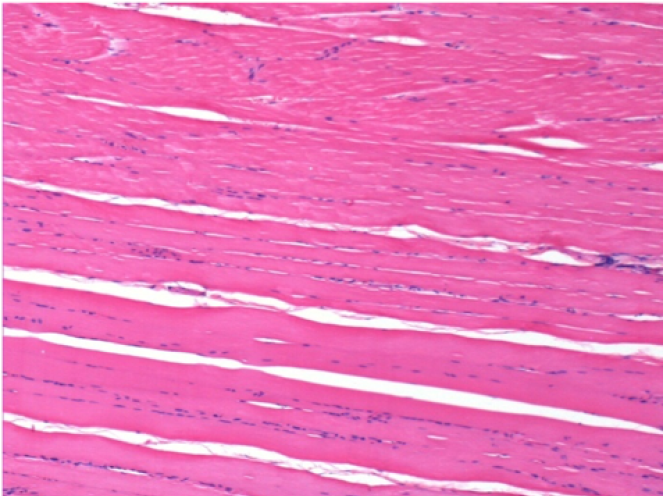

3 meses después de la inyección de Endopeel

3 meses (D90) después de la inyección de Endopeel 0.1ml en el músculo pretibial derecho.

L : Control-100xD90

R:100xD90